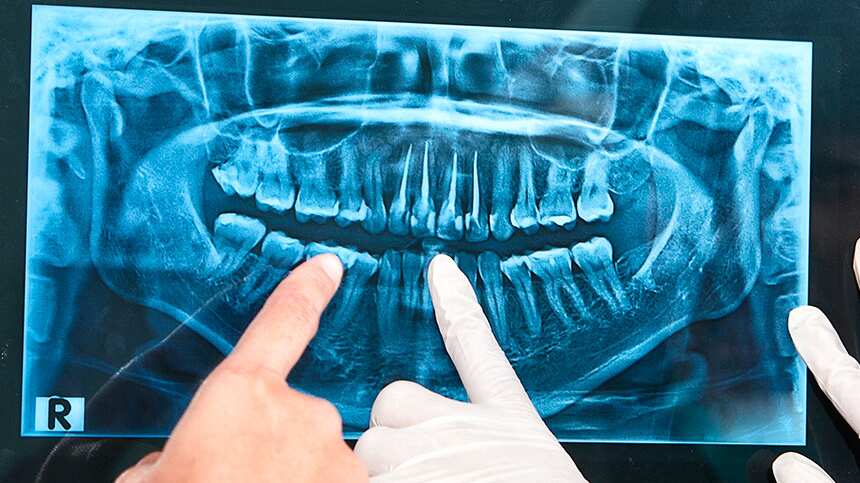

Para ello, este requiere de una radiografía panorámica, recurso que le permitirá trabajar con concisión y con el mínimo margen de error.

Señala la Odontóloga Teruelo De Luis que “una vez que hemos realizado una radiografía panorámica, hago una exploración de la boca y comento con el paciente sobre las patologías existentes, en el caso de haberlas, y de los tratamientos a aplicar de manera totalmente personalizada”.

Así mismo, en el citado sitio web se agrega que “la radiografía panorámica es la prueba diagnóstica más importante dentro de las que se realizan en la primera visita a la clínica dental, por tanto, nos permite observar el estado de los dientes, de los huesos maxilares, articulación temporo-mandibular (ATM), ligamentos, etc, con una gran nitidez. Esto nos ayuda a observar de manera general y completa el estado bucal de nuestros pacientes y, a partir de ahí, diagnosticar y tratar los problemas dentales”.